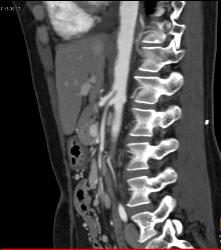

Plaque in Proximal SMA